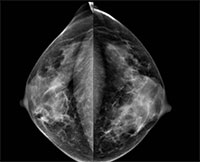

Prior research has shown an association between breast density and breast cancer. In addition, cancers in dense breast tissue are more difficult to see on mammograms. As a result, some women with dense breasts are advised to get supplementary screening with ultrasound or MRI. Some U.S. states have enacted legislation mandating breast density reporting to women undergoing mammography.

Two radiologists read the mammograms independently and determined breast density according to standard criteria. The researchers compared data between patients in the low-density breast tissue group and the high-density group.

The majority of screened woman had low breast density. Of the 230 detected breast cancers, almost half were from the group with the lowest ranked breast density, while slightly less than 3 percent came from women in the highest breast density category.

When the researchers matched the women who had a detected cancer with control participants of the same age and from the same locales who did not have cancer, they found no significant difference in mammographic density. Women with low mammographic density made up 83 percent of the patients in the breast cancer group, compared with 89 percent in the control group, while high mammographic density was found in 17 percent of the breast cancer patients and 11 percent of women in the control group.